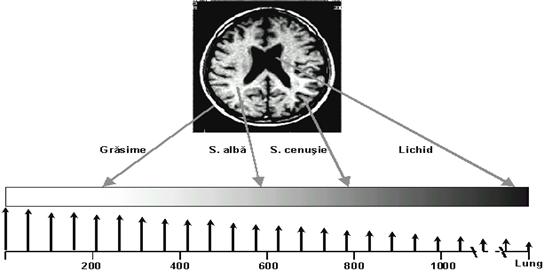

CONTRASTUL T1

Tesutul adipos are timpul T1 cel mai

scurt, apare alb, (hipersemnal)

Lichidele, au T1 cel mai lung, se situeaza

la extrema opusa, fiind negre (hiposemnal).

Celelalte tesuturi se

incadreaza intre aceste doua limite extreme, in functie de

timpii lor T1.

Contrastul T1 a diferitelor structuri craniene